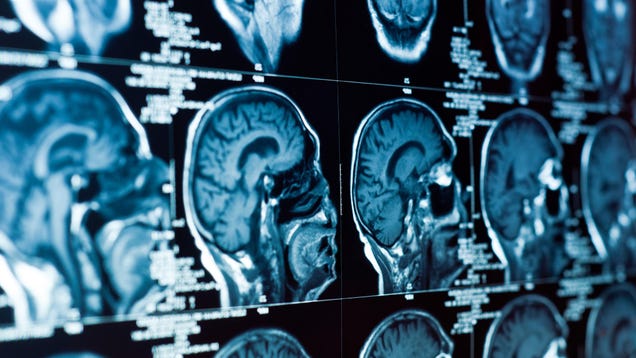

New research this week suggests that an aggressive brain cancer can hijack the brain’s own circuitry to further spread and render itself unstoppable. Researchers in Germany studied glioblastoma cells in mice and in the lab, finding that these tumors use some of the same mechanisms behind normal neuron development and…

Source: Gizmodo – A Deadly Cancer Hijacks the Brain to Render Itself Untreatable, Study Finds